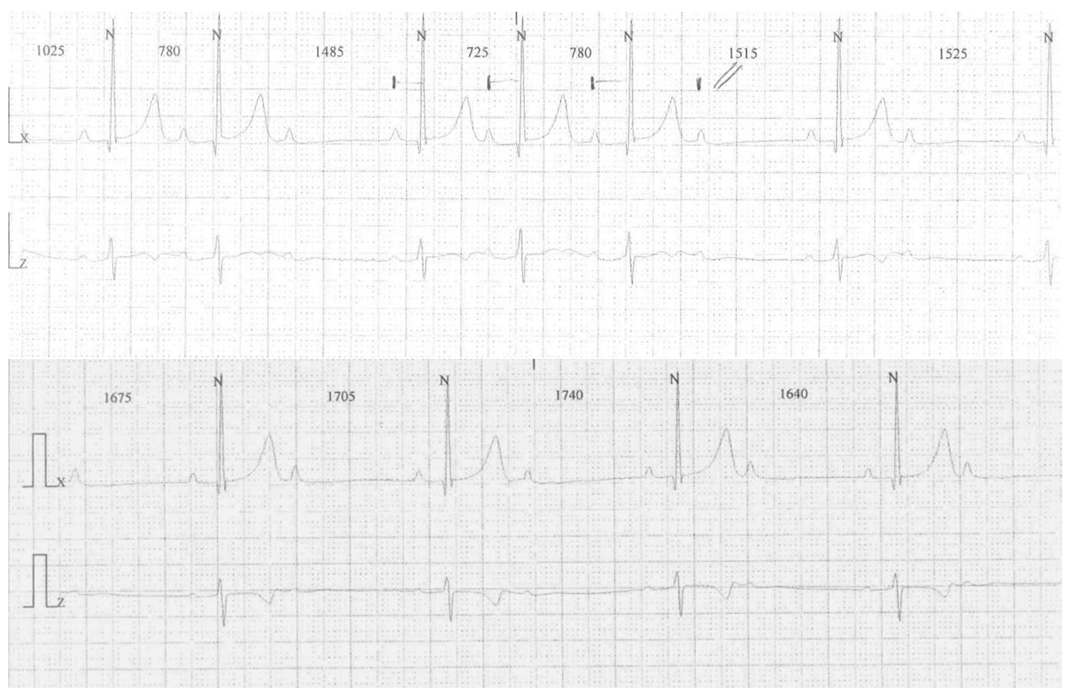

Atrioventricular Block in Celiac Disease: An Unusual Clinical Presentation in a Child. A Case-Based Review

2. Case Presentation